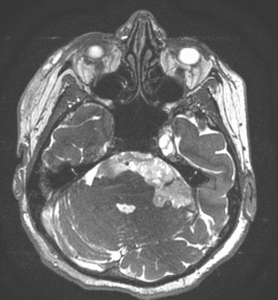

Imagistica prin rezonanță magnetică (IRM):

- Investigația de elecție.

- Chisturile epidermoide:

- Hiposemnal T1, hipersemnal T2.

- Nu se încarcă cu substanță de contrast.

- Apare restricție de difuzie pe secvențele DWI – caracteristică importantă.

- Chisturile dermoide:

- Hipersemnal pe T1 (datorită conținutului lipidic).

- Semnal mixt pe T2.

- Poate avea semnal susceptibil pe secvențe GRE dacă există componente calcificate.

- Poate fi evidentă o fistulă cu exteriorul.